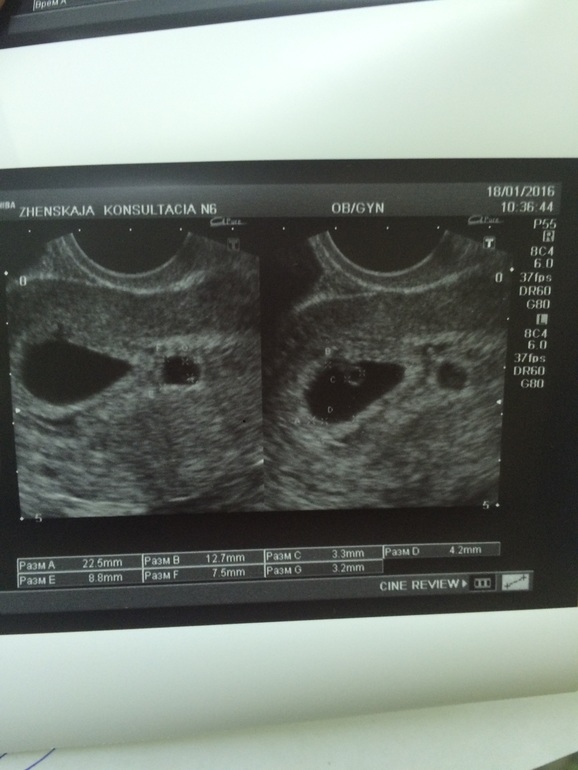

УЗИ, КТГ, доплер, скрининг, ХГЧ и другие анализыбыла на узи. Один эмбрион 6 нед сб+ второй просто пя с желточным мешочком. Под вопросом поставили не развивающиеся второе пя, сказали, что шансы почти равны нулю( есть шанс что малыш появится? Контроль 28.01